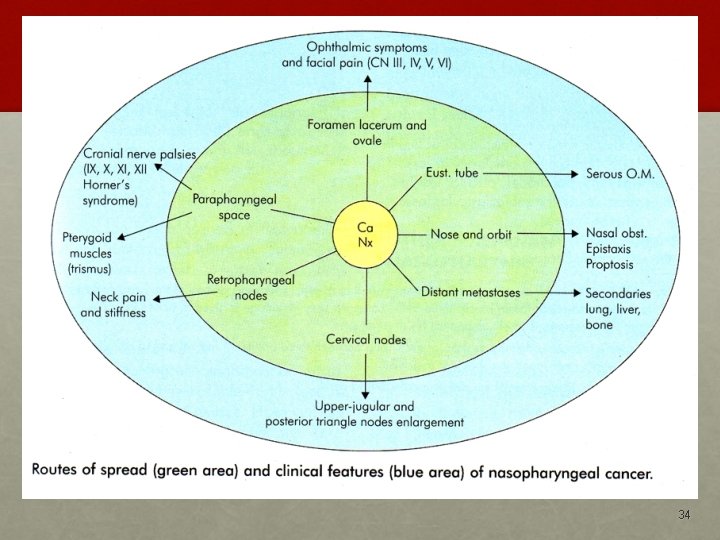

spread

Cervical Lymphadenopathy (60%) • tendency for early lymphatic spread • commonest palpable node – jugulodiagastric • contralateral lymph nodes metastasis (nasopharynx is midline structure) 35

Aural Symptoms • NPC leads to eustachian tube occlusion ü sensation of a blocked ear ü impaired hearing ü tinnitus ü u/l serous otitis media 36

Epistaxis and Nasorespiratory Symptoms • blood stained nasal discharge • profuse epistaxis • nasal obstruction • Hyponasal speech 37

Neurological Palsies • Most frequently involved are: ü VI - Lateral rectus palsy - Diplopia & squint ü III, IV, VI - are commonly affected together (opthalmoplegia) ü V – Facial pain & paraesthesia ü IX, X & XI - Jugular Foramen Syndrome (involvement of the IX, X, and XI CN) • Isolated single C. N. palsy common with nerves V & VI • Horner’s syndrome 38